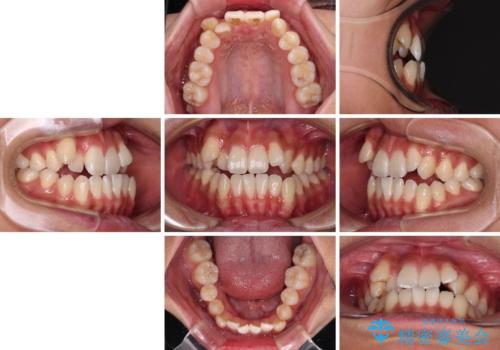

- 前歯の開咬と、上顎前歯の八重歯やデコボコを気にして来院された患者様です。

上顎歯列が狭窄していたため、急速拡大装置により上顎骨を側方に拡大し、その後ワイヤー装置にて矯正治療を行うこととしました。